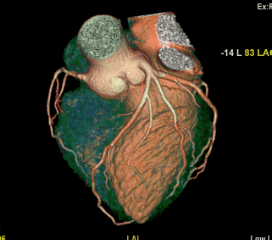

Coronary Angiogram

A CT Coronary Angiogram is a non-invasive imaging test that uses a CT scanner, and contrast dye to create detailed 3D pictures of your heart's arteries, revealing plaque, blockages, or narrowing (stenosis) that can cause heart problems like chest pain.

3D Vessel Analysis